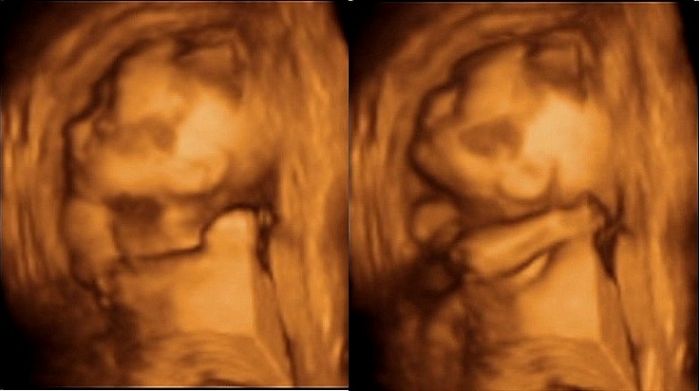

Ahoj holky,tak máme 3D UZ za sebou,ale teda čekala jsem od toho asi víc,po tom co sem tu viděla i opravdu nádherné a detailní fotky..

Doufala jsem,že ta tvářička bude vidět líp,ale to prý bývá nejhezčí až tak kolem 28tt..

Hlavně teda mrňous totálně nespolupracoval,ale co by jsme chtěli,když má svojí hlavinku a včera ukázal že nejspíš pěkně tvrdohlavou..

Na začátku spinkal,tak to trošku šlo,až na to,že ležel z profilu...Když už se vzbudil,odmítal dát ručičky pryč z obličeje a když už se nám pak po několika převaleních a dřepech podařilo ho trošku probrat,začalo naopak rodeo..

Měla sem pocit,že chytil jakýsi záchvat zuřivotsi,protože měl pusinku dokořán jakoby brečel nebo křičel,ručičkama tam mával zlostně kolem hlavičky a hlavičkou prudce otáčel ze strany na stranu,nahoru dolu až mě ho bylo líto,když sem viděla jak vyvádí..

Nakonec mu chudince došla trpělivost,tak usnul a otočil se úplně zády s rukou za hlavou,takže nám dal jasně najevo kde mu už asi jsme a ať ho necháme být..

Taky teda ještě asistentka říkala,že když je placenta na přední straně,je tam ta viditelnost prý mnohem horší,než když je uložená vzadu za miminkem a u nás to k tomu ještě komplikoval fakt,že ty placenty mám dvě,přesně naproti sobě a mrňous byl mezi ně dost natěsno..

Takže asi tak no...Nemůžu říct,že to nebyl hezký zážitek a vzpomínka,aleza ty peníze sem asi čekala trošku lepší výsledek..

POsílám pár 3D fotek + 2D fotku dvou placent..